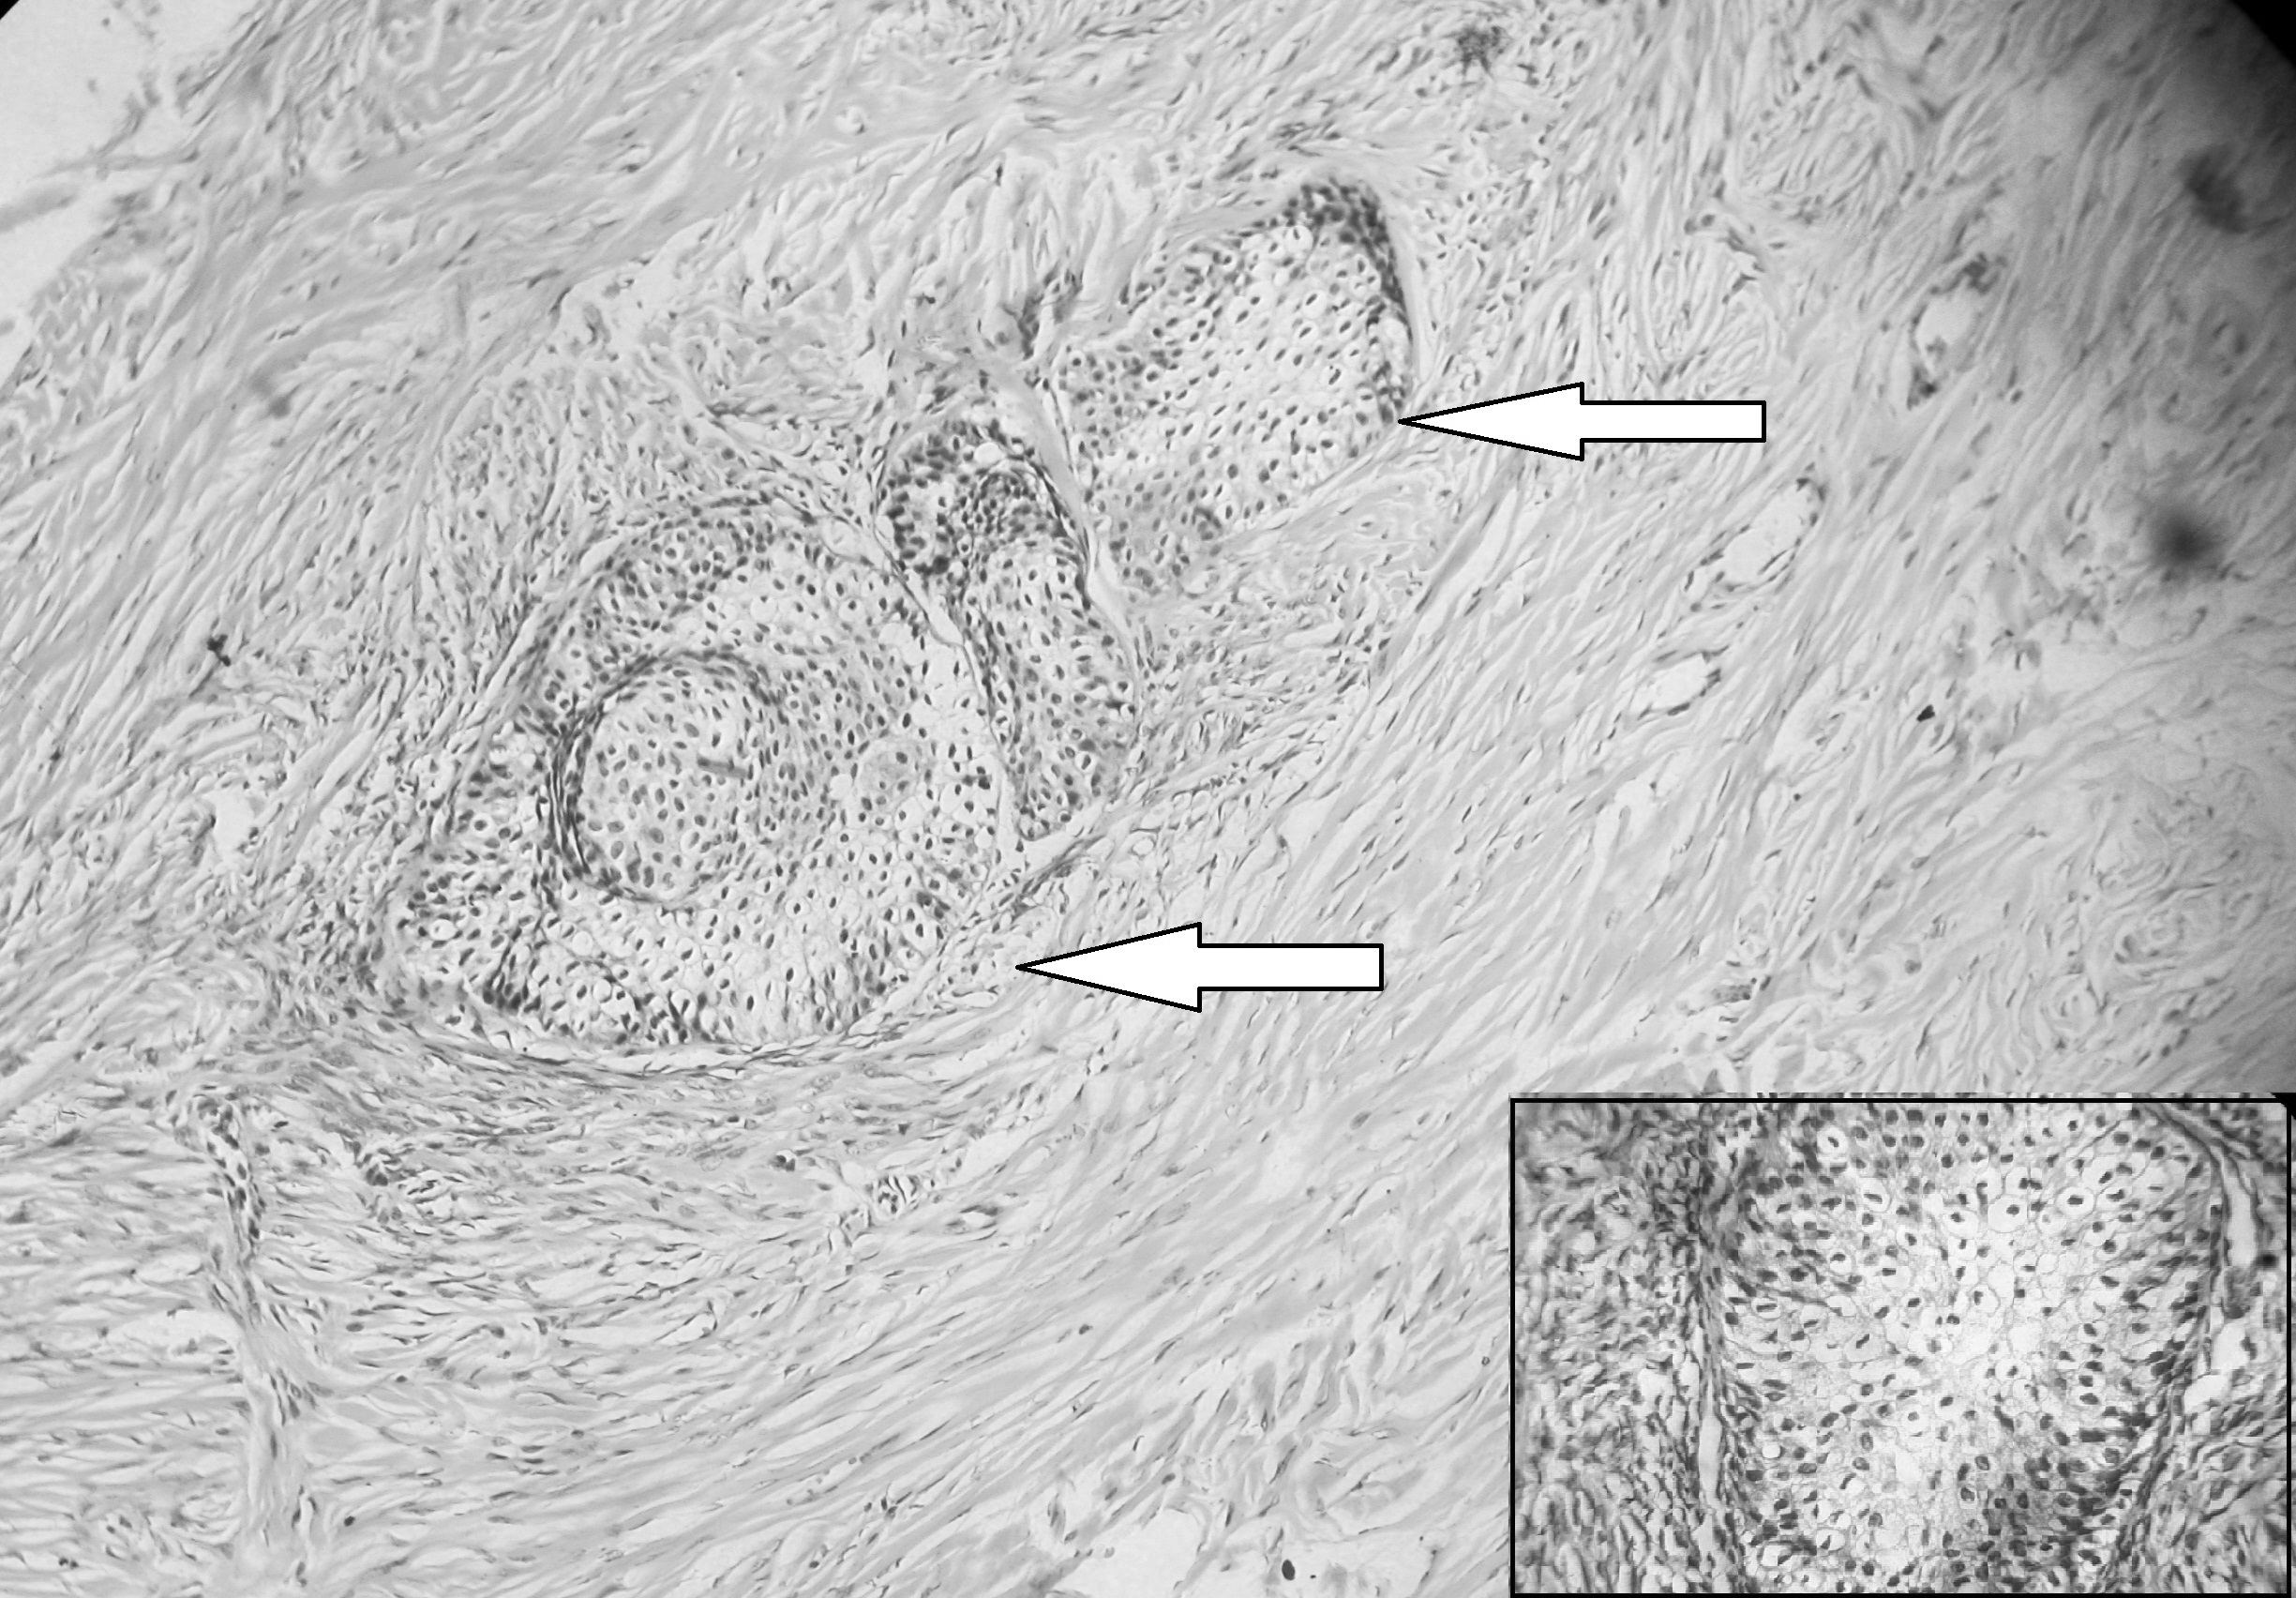

Results: A total 52 ovarian tumors were included in this study. Most common histological types were surface epithelial tumors (92.3%), out of which 54.2% were benign, 41.7% were malignant and 4.2% were borderline. Serous cystadenoma was the most common benign tumor and serous cystadenocarcinoma was the commonest malignant tumor. Abdominal discomfort was the commonest presenting symptom both in benign and malignant tumors (85.7% and 45.4% respectively). Most of the malignant tumors were presented in stage III (50%), followed by stage II (27.3%).